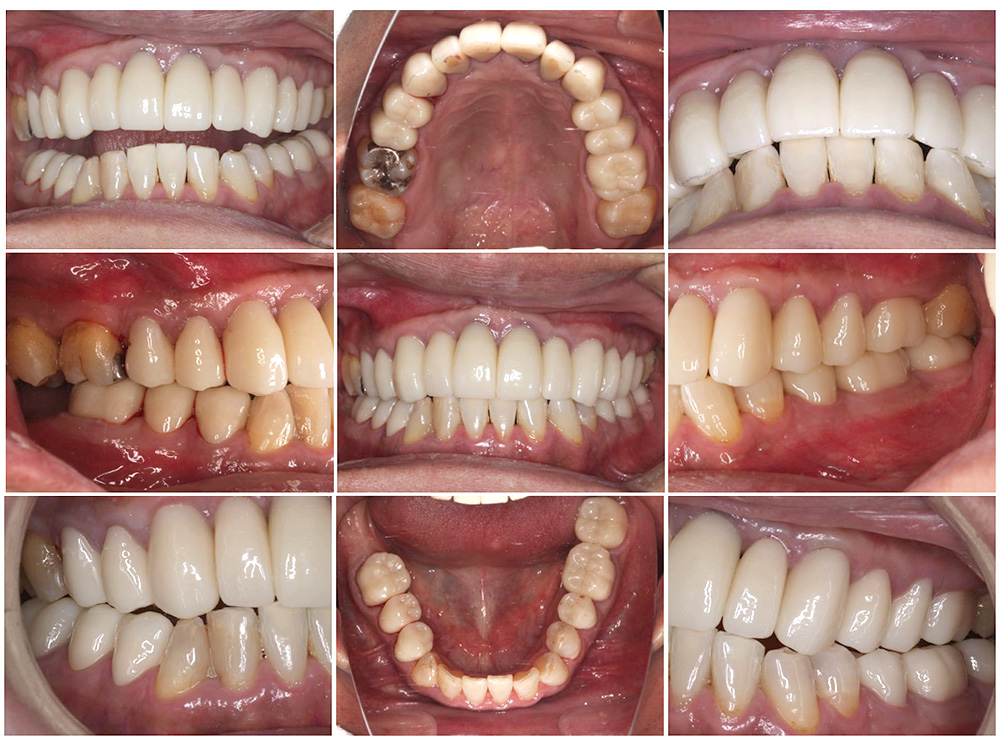

症例紹介